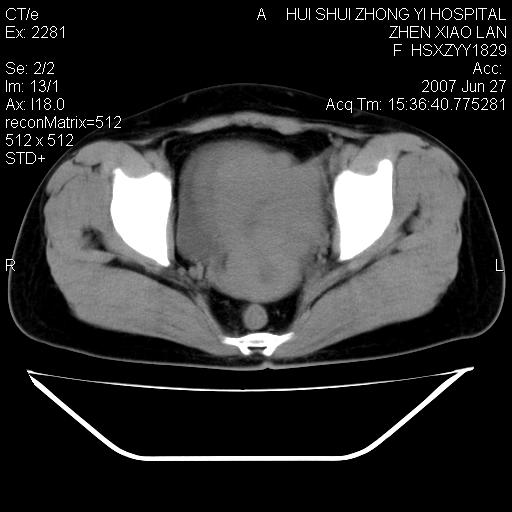

以下是引用还珠格格在2007-6-28 15:15:00的发言:[br]子宫明显增大,偏向盆腔右侧,密度均匀,和子宫同密度, 考虑 子宫肌瘤可能性大 建议增强 除外子宫平滑肌肉瘤。

以下是引用dyqct在2007-6-28 15:41:00的发言:[br]考虑多发子宫肌瘤可能性大,建议进一步增强检查。